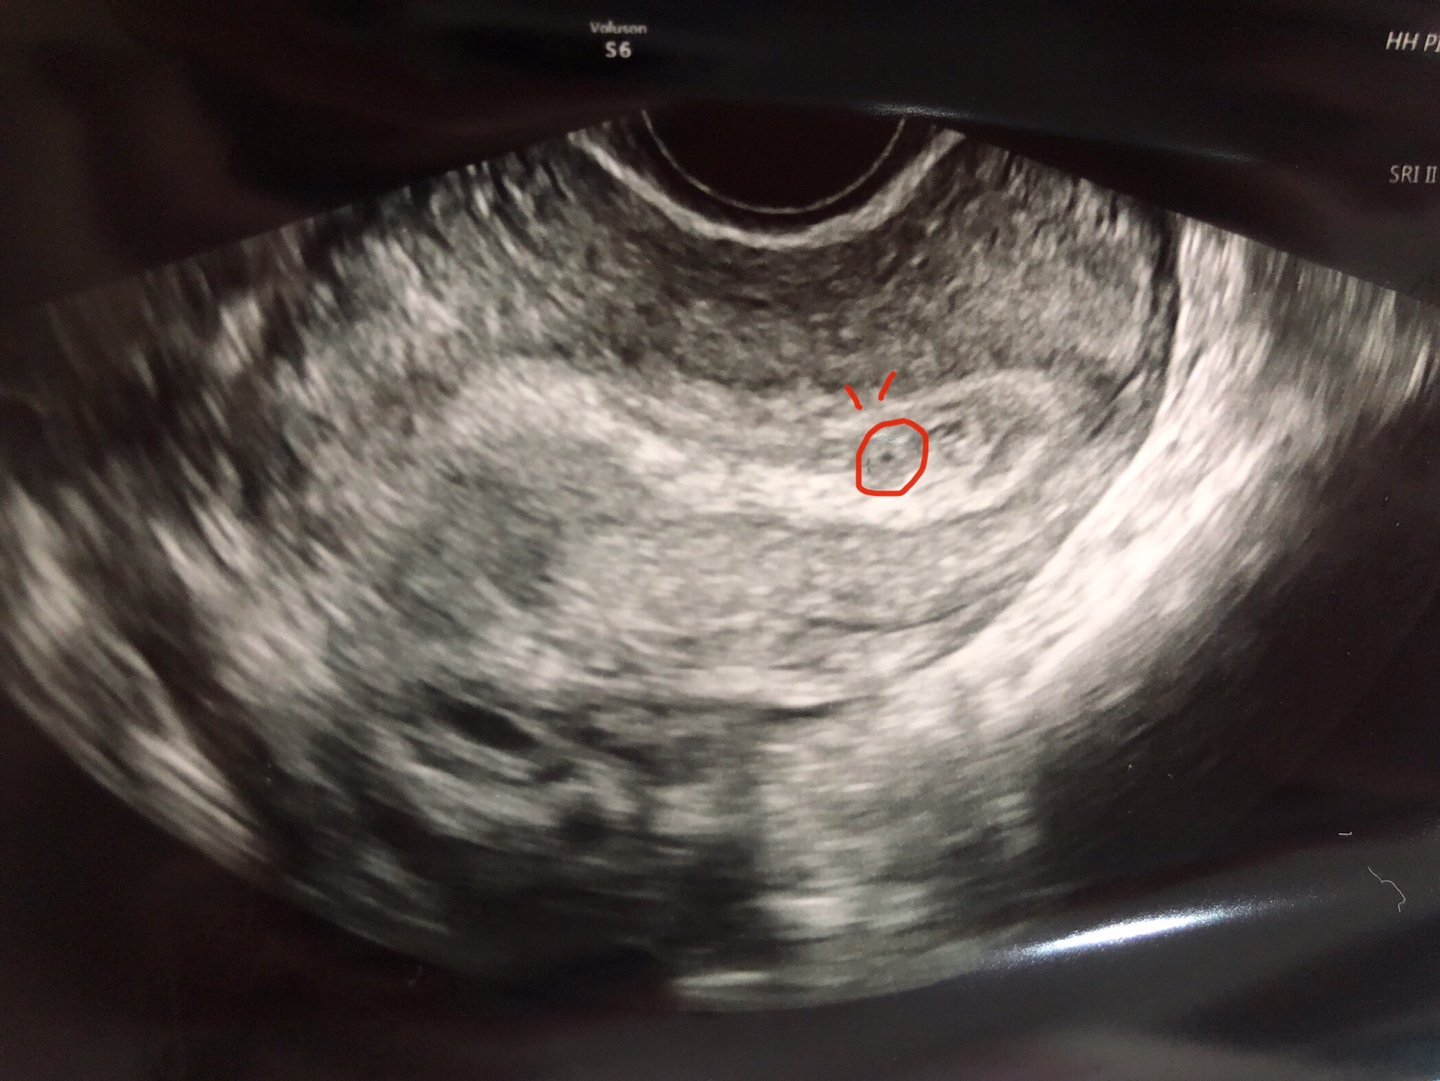

축하해 주세요! 여러분! 새로운 식구가 생겼습니다. 아들인지 딸인지 말랐는지 뚱뚱한지 키가큰지 작은지 똑똑한지 재주꾼인지 알 수는 없지만! 저 사진속 가운데에 있는 저 조그마한 녀석이 바로 피피의 새식구 '알콩이' 입니다.